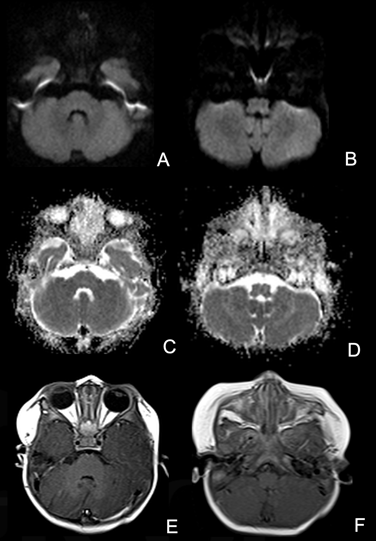

Figure 2 (A–D) Axial diffusion-weighted images (DWI) and apparent diffusion coefficient (ADC) images do not show acute ischemic lesions. (E,F) Axial T1 post contrast images do not reveal contrast enhancement.